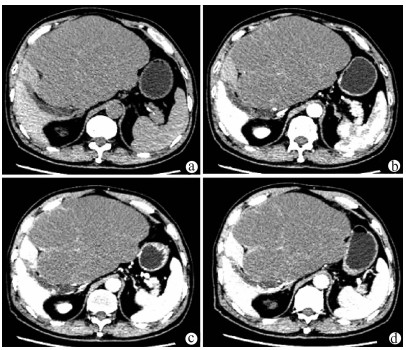

Effectiveness and safety of two-step percutaneous transhepatic choledochoscopic lithotomy in treatment of complex hepatolithiasis

Changhu DUAN, Xiaochen LIU, Jianfeng DUAN, Jianlong DING, Xirong ZHAO, Fan YANG, Lin WU, Lifei ZHAO, Sheng TAI

2021, 37(11): 2636-2641. DOI: 10.3969/j.issn.1001-5256.2021.11.029

Abstract(1120) HTML (790) PDF (1978KB)(89)

Abstract:

Objective  To investigate the clinical effect of two-step percutaneous transhepatic choledochoscopic lithotomy (PTCSL) in the treatment of complex hepatolithiasis.  Methods  A retrospective analysis was performed for the clinical data of 118 patients with complex hepatolithiasis who were admitted to 3201 Hospital of Xi'an Jiaotong University Health Science Center from January 2018 to June 2020, and according to the surgical procedure, they were divided into PTCSL group with 60 patients and surgery group with 58 patients. All patients were followed up for half a year to 3 years via telephone and outpatient service. The two groups were compared in terms of general information, perioperative indicators (including time of operation, intraoperative blood loss, incision length, time to first flatus and time to first defecation after surgery, time to extraction of abdominal drainage tube, and length of hospital stay), changes in liver function and inflammatory indicators, postoperative complications (bile leakage, acute cholangitis, wound infection, and venous thrombosis of lower extremities), stone clearance rate and recurrence rate, and quality of life. The two-independent-samples t-test was used for comparison of continuous data between two groups; the paired t-test was used for comparison between different periods of time within group; the chi-square test was used for comparison of categorical data between two groups.  Results  Compared with the surgery group, the PTCSL group had significantly shorter time of operation, time to first flatus and time to first defecation after surgery, and time to extraction of abdominal drainage tube, a significantly lower intraoperative blood loss, and a significantly shorter incision length (all P < 0.05). On day 1 after surgery, both groups had significant reductions in alanine aminotransferase (ALT) and aspartate aminotransferase (AST) (P < 0.05) and a significant increase in white blood cell count (WBC) (P < 0.05), and the PTCSL group had significantly lower levels of ALT, AST, and WBC than the surgery group (all P < 0.05). Compared with the surgery group, the PTCSL group had significantly lower incidence rates of postoperative bile leakage (5.0% vs 17.2%, P < 0.05), acute cholangitis (3.3% vs 13.8%, P < 0.05), wound infection (1.7% vs 10.3%, P < 0.05), and venous thrombosis of lower extremities (1.7% vs 12.1%, P < 0.05). Compared with the surgery group, the PTCSL group had a significantly higher stone clearance rate (58.3% vs 37.9%, P < 0.05) and a significantly lower long-term stone recurrence rate (10.0% vs 20.7%, P < 0.05). The PTCSL group had significantly higher quality of life scores than the surgery group (all P < 0.05).  Conclusion  For the treatment of complex hepatolithiasis, two-step PTCSL can effectively remove stones, with the advantages of fast postoperative recovery, low recurrence rate and incidence rate of complications, and high quality of life, and therefore, it is an effective alternative surgical procedure.